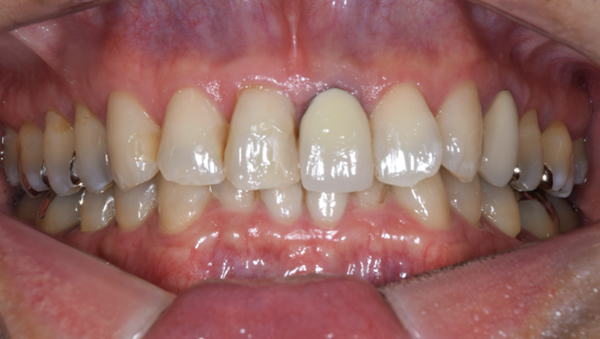

症例1

治療前

治療後

治療内容

口腔内の銀歯を全てセラミックにしたいというご希望でした。親知らずは抜歯しています。笑ったときや自然なスマイルをしたときも銀歯が見えなくなり自然になりました。

治療期間 約2ヶ月

治療費 合計:935,000円 (内訳)

オールセラミック:110,000円×5本

セラミックインレー:55,000円×7本

治療のリスク・副作用 銀歯の下で虫歯が大きくなっていたら歯の中の神経をとらないといけないことがあります。また、被せ物を外すと、ご自身の歯が少ない場合は別途はを残すための処置が必要になることがあります。